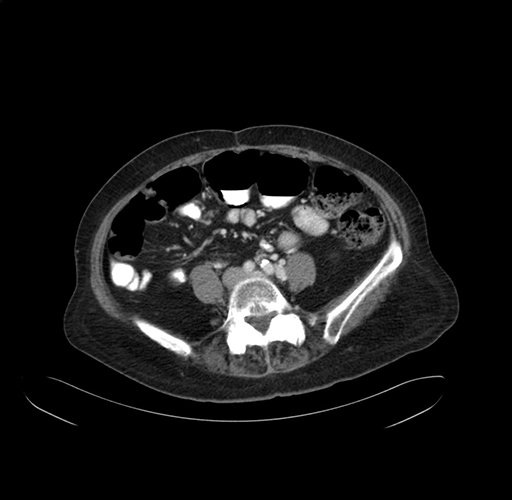

Pre-Chemo: Axial Venous

Axial Venous